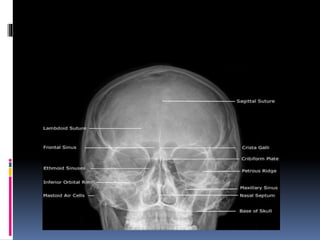

 CALDWELLVIEW

 A/K/A OCCIPITOFRONTAL VIEW OR NOSE

FOREHEAD POSITION

 Part Position

 Place patient's nose and forehead against upright

table with neck extended to elevate the OML 15°

from horizontal. A radiolucent support between

forehead and upright Bucky or table may be used

to maintain this position. CR remains horizontal.

(alternate method if Bucky can be tilted 15°.)

 Center X-RAY to CR and to nasion, ensuring no

rotation.

 Align CR horizontal, parallel to floor.

POSITION: SINUSES Caldwell Method

STRUCTURES SEEN

1. FRONTAL SINUSES (SEEN BEST)

2. ETHMOID SINUSES

3. MAXILLARY SINUSES

4. FRONTAL PROCESSOF ZYGOMA AND

ZYGOMATIC PROCESSOF FRONTAL BONE

5. SUPERIOR MARGIN OF ORBIT AND LAMINA

PAPYRACEA

6. SUPERIOR ORBITAL FISSURE